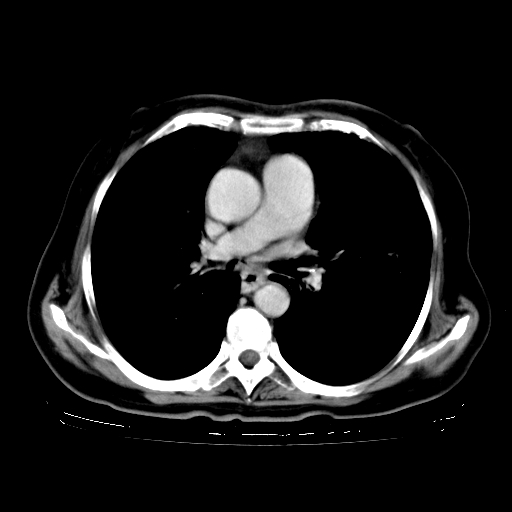

女,70岁,咳嗽、咳痰一个月,低热一周。

1.左上肺结核,部分纤维化。右肺中下叶部分肺不张,内见液化、坏死及点状钙化,右中下叶支气管壁增厚、管腔狭窄,见多个点状钙化,结合临床考虑支气管内膜结核,建议痰检查抗酸杆菌并参考血沉。两肺多个小圆点状高密度灶,境界模糊,多考虑结核肺内播散。但本人年龄较大首先应支气管镜检以除外右肺癌。

2.胸主动脉夹层。

支持,首先一元论解释。胸主动脉部分层面环形低密度,中心强化。环形影不强化。不象真假腔的改变。我考虑动脉炎,不太支持夹层动脉瘤-和大家的观点不一致,希望楼主让患者再做个心血管的彩超吧。